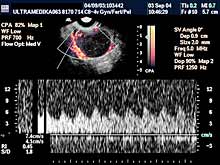

- CPD-ova tehnika "broji" eritrocite i registruje intenzitet

protoka. Za razliku od konvencionalne CD tehnike omogućava

određivanje otpora (Reziostent-nih i Pulzativnih indeksa) u

najsitnijim krvnim sudovima koji se formiraju u početku rasta

tumora.

- 3D CPA je multiplanarna analiza kodiranih krvnih sudova organa male

karlice, ili novofomiranih tkiva-tumora, radi preciznije i tačnije

dijagnoze. Procena krvnih sudova grlića - ovom tehnikom - je obavezni

deo pregleda organa male karlice.